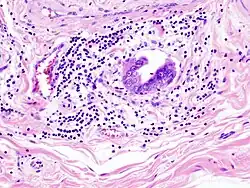

Invasão linfática de adenocarcinoma na vesícula biliar capturada numa histopatologia